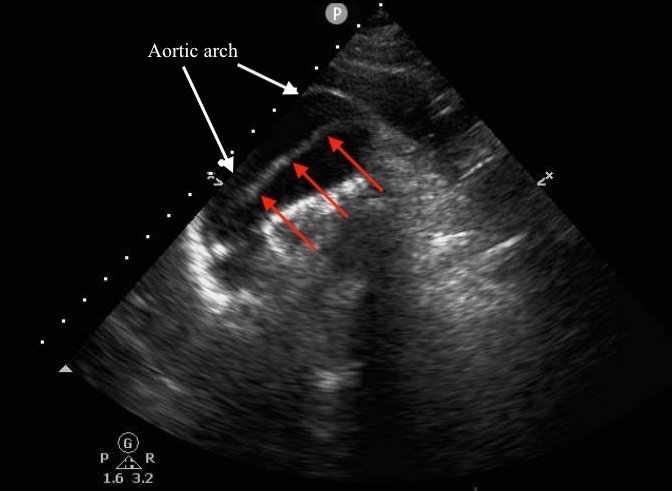

Aortic dissection is a life-threatening, time-sensitive emergency. Conventional diagnostic imaging modalities such as computed tomography (CT) can be time-consuming to obtain, and require that the patient leave the emergency department (ED); as such, they are unsuitable for unstable patients. Emergency focused transthoracic echocardiography (ETTE) is commonly performed in the ED as part of the evaluation of a patient presenting with chest pain, but the suprasternal notch view (SSNV) is much less well-known and infrequently included in this assessment.

We present a case of a 51-year-old previously healthy man who presented to the ED complaining of chest pain that had resolved prior to arrival, and a mild headache. His vital signs were notable for hypotension, but physical exam was unremarkable. Chest x-ray revealed a borderline widened mediastinum. A standard ETTE was within normal limits, but additional SSNV demonstrated a dissection flap in the aortic arch. The patient was taken to the operating room for surgical repair 75 minutes after the ED ultrasound was performed; the operation was successful, and the patient was discharged to home post-operatively with good outcome.

Standard ETTE has limited ability to visualize the ascending aorta and aortic arch. Addition of SSNV allows visualization of these structures and may improve diagnostic accuracy and time to diagnosis of proximal aortic dissection.